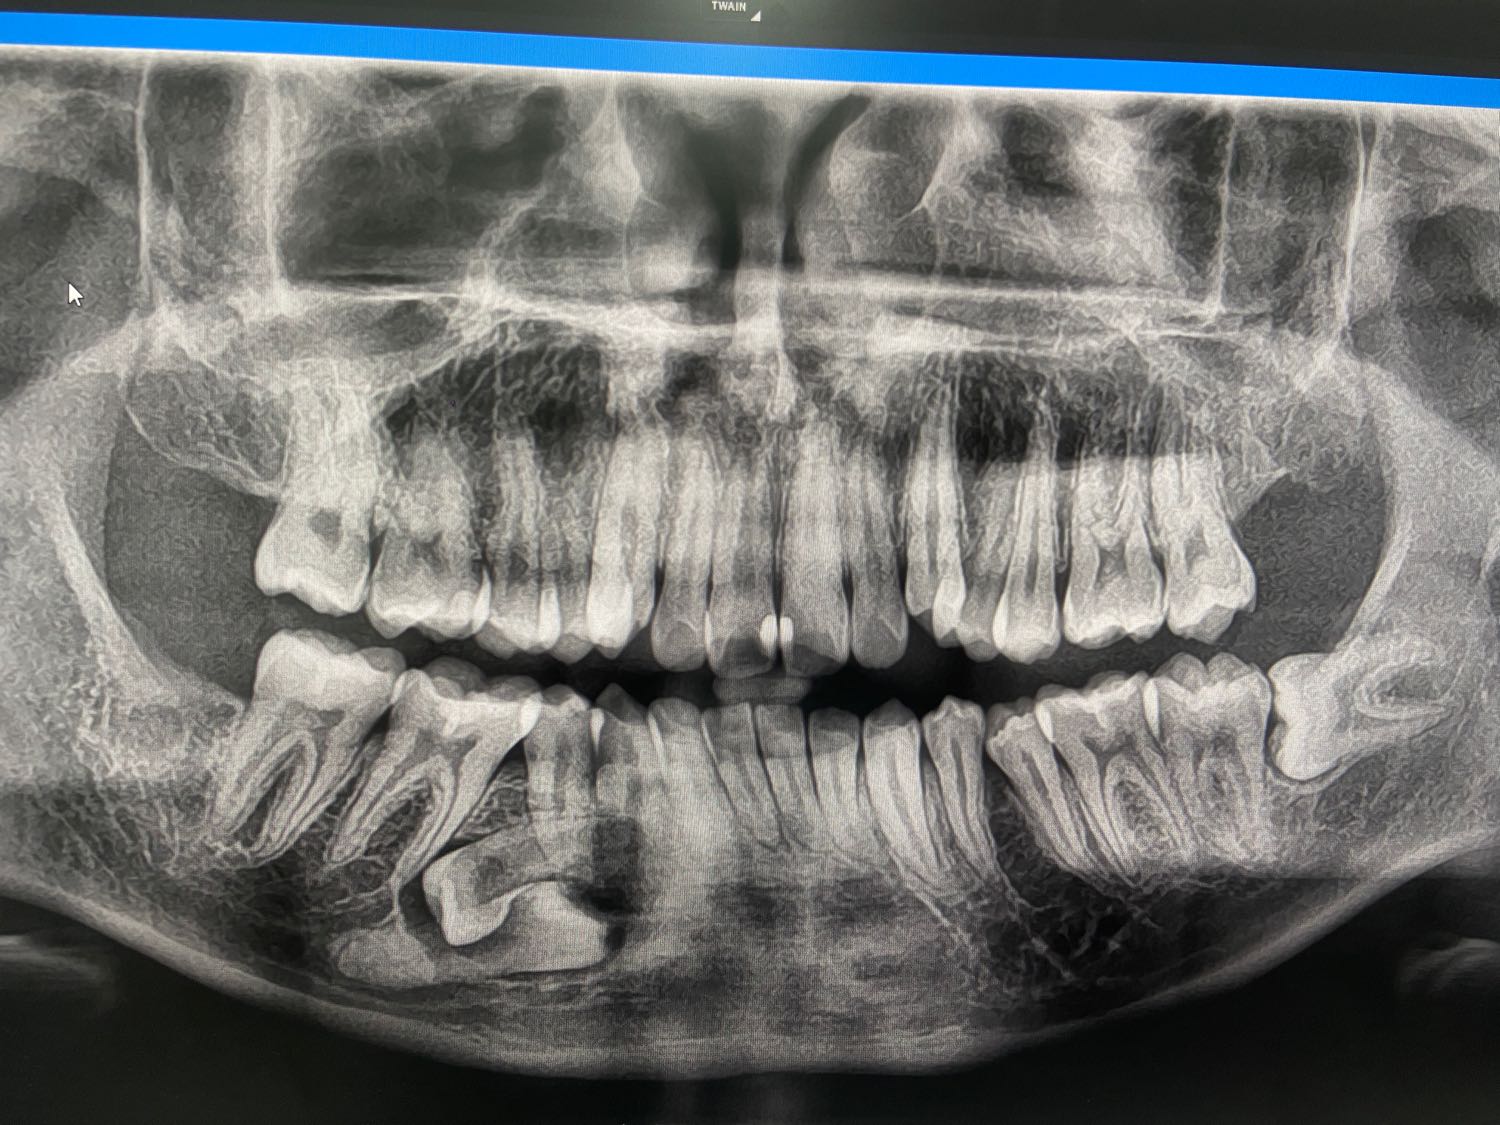

ผมพึ่งอายุ18 พึ่งเจอฟันฝัง2ซี่ แบบนี้ต้องเอาออกไหม ตอนที่ไปคลินิกผมไป x-ray อย่างเดียวไม่ได้ปรึกษา

ถ้าต้องเอาออก อยากทราบอาการว่าเป็นไงบ้าง ราคาเท่าไหร่ ผ่า รัฐหรือคลินิก